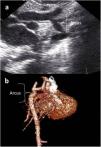

Images were reconstructed to 0.6 mm in thickness and to a reconstruction interval with a 25f kernel filter; they were processed on a separate workstation (Vitrea, Vital Images Inc., Minnetonka, MN) with multiplanar reformatting, maximum-intensity projection, and volume rendering (Figures 1 and 2). Multidetector CT images were prospectively reviewed by two radiologists with 15 (AT) and five (CT) years experience in cardiovascular imaging, and decisions were made by consensus.

Two-year-old female patient with septum primum malposition and partial anomalous pulmonary venous return. (a) Modified 4-chamber view on echocardiographic examination; (b) computed tomography images in axial view. ASD: atrial septal defect; IAS; interatrial septum; IVS: interventricular septum; LA; left atrium; LLPV: left lower pulmonary vein; LUPV; left upper pulmonary vein; LV: left ventricle; RA; right atrium; RLPV: right lower pulmonary vein; RUPV: right upper pulmonary vein; RV: right ventricle.